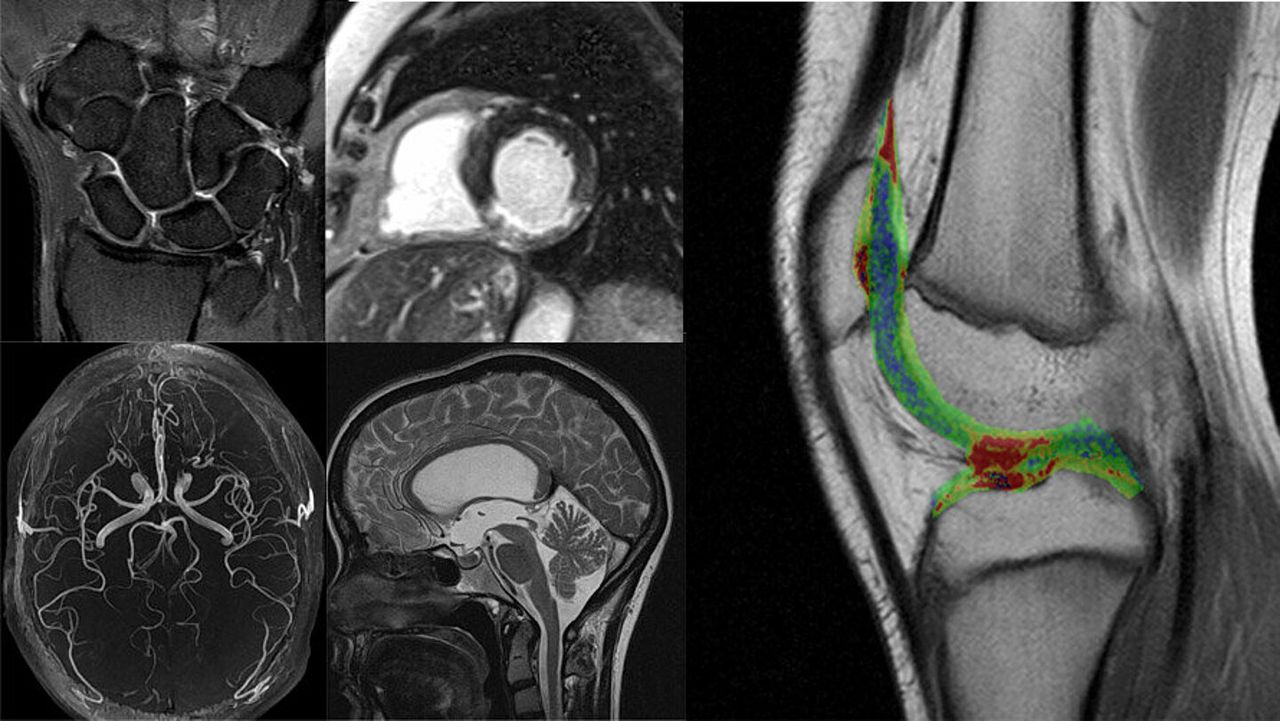

Unsere offene Niederfeld-MRT (Fuji Aperto Lucent plus, 0,4 Tesla) ist sehr schonend für den Patienten (die elektromagnetische Strahlung beträgt nur ca. 1% eines Hochfeldgerätes).

Das offene Design ist besonders geeignet für Patienten mit Platzangst, bei Übergewicht, für Kinder, in der Schwangerschaft und für Patienten mit Fremdkörpern oder Implantaten.

Sie bietet einen guten T1-Kontrast, wenig Bildstörungen durch Bewegung oder Metalle, insbesondere bei Implantaten oder Fremdkörpern.

In unserem offenen Niederfeld MRT bieten wir Diagnostik für folgende Bereiche:

- Hals-, Brust- & Lendenwirbelsäule

- Gelenke mit Sehnen, Bändern & Muskulatur

- Kopf

- Halsweichteile

- Bauchraum

- Beckenorgane weibl. & männl.

- Mamma- & Prostata-MRT bei Platzangstpatienten